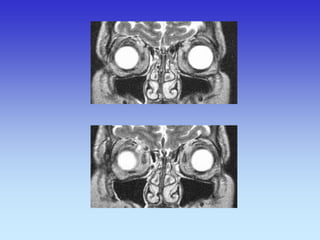

Upala sinusa

CT SINUSA

MMAKSILARNI SINUSI

ETMOIDINI SINUS